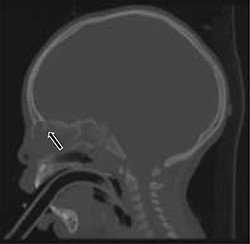

A total of fourteen patients were identified. The age range of these patients was 6 months to 17 years. There was an equal gender distribution. An average of 11 weeks lapsed between initial presentation and definitive excision. All patients underwent MRI; all patients exhibited an abnormality, most commonly isointense T1 and hyperintense T2 soft tissue findings in the area of the nasal dorsum/glabella (Fig. 2). Eleven of the fourteen patients (78.6%) underwent a CT. Of those eleven patients, two patients exhibited a splaying of nasal bones (Fig. 3). Fifty percent of the patients required preoperative antibiotics for infected nasal dermoid cysts; one patient was admitted to the infectious disease service for intravenous antibiotic therapy prior to formal surgical excision. One of the fourteen patients (7.1%) had a formal excision with a rhinoplasty approach, while the majority thirteen of the fourteen patients (92.8%) underwent an open vertical incision for the surgical approach. Four of the fourteen patients (28.5%) had recurrent infection and required additional surgery. Three of seven patients required incision and drainage prior to definitive excision. One of seven patients in the infected group had recurrence. Three of the seven patients in the non-infected group recurred. Bacterial cultures in all of these patients did not identify common pathogens. Surgical pathology revealed acute on chronic inflammation in 50% of cases; three of the fourteen patients (21.4%) revealed multinucleated giant cells on microscopic analysis. Two of the fourteen total patients had intracranial extension. None of these patients developed meningitis.

T2-weighted sagittal MRI of hyperintense soft tissue findings in the setting of a nasal dermoid cyst penetrating the anterior cranial fossa.